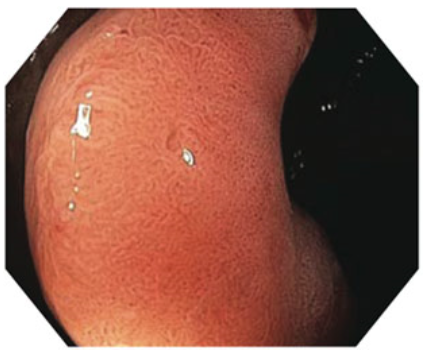

Dual focus two-stage optical lens technology from Olympus allows physicians to switch from normal focus mode to near focus mode with a single button, so they can conduct close examination of mucosal tissue and capillary networks. This technology lets physicians select the desired depth of field and obtain images at the same time.

Near Focus Mode

(Near) Mode: 6mm – 2mm

Normal Focus Mode

(Normal) Mode: 100mm – 5mm